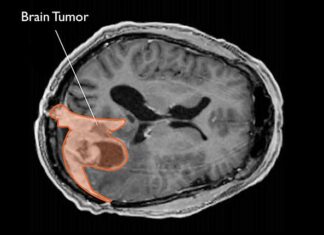

¿Cuáles son los tratamientos que se utilizan para el meningioma?